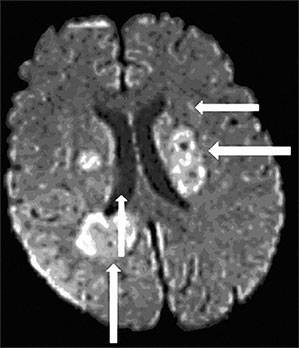

- неврологическими симптомами (сонливостью, нарушением сознания, головными болями, головокружениями), что может быть принято за симптомы микроинсульта или инсульта головного мозга;

Если больной переживает последствия инсульта, то на первый план может выйти спутанность сознания и дыхательные расстройства.

Так, при патологиях сердца и сосудов характерной будет симптоматика, свидетельствующая о недостаточности этих органов. Инсультное состояние в первую очередь проявляется сбоем в работе лёгких и изменениями сознания.